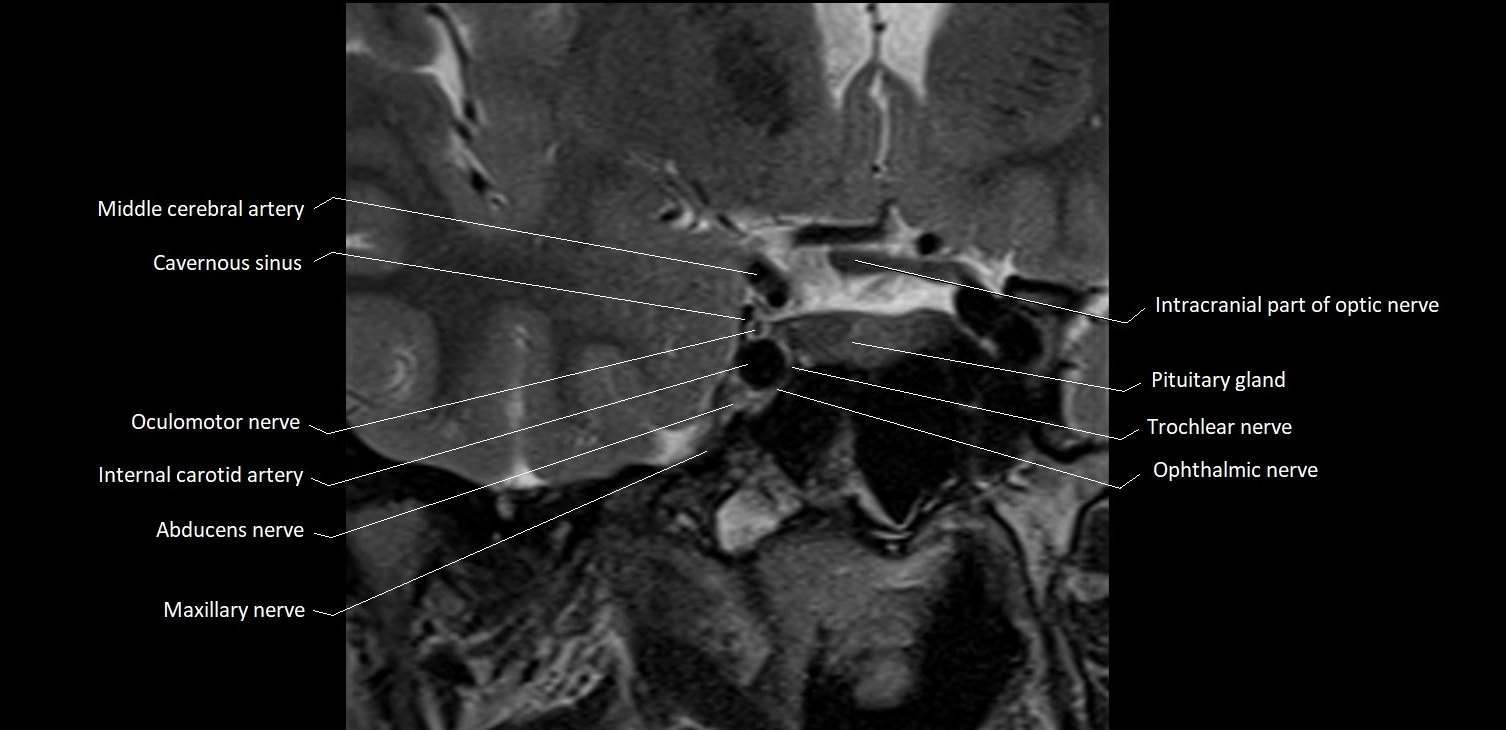

MRI images